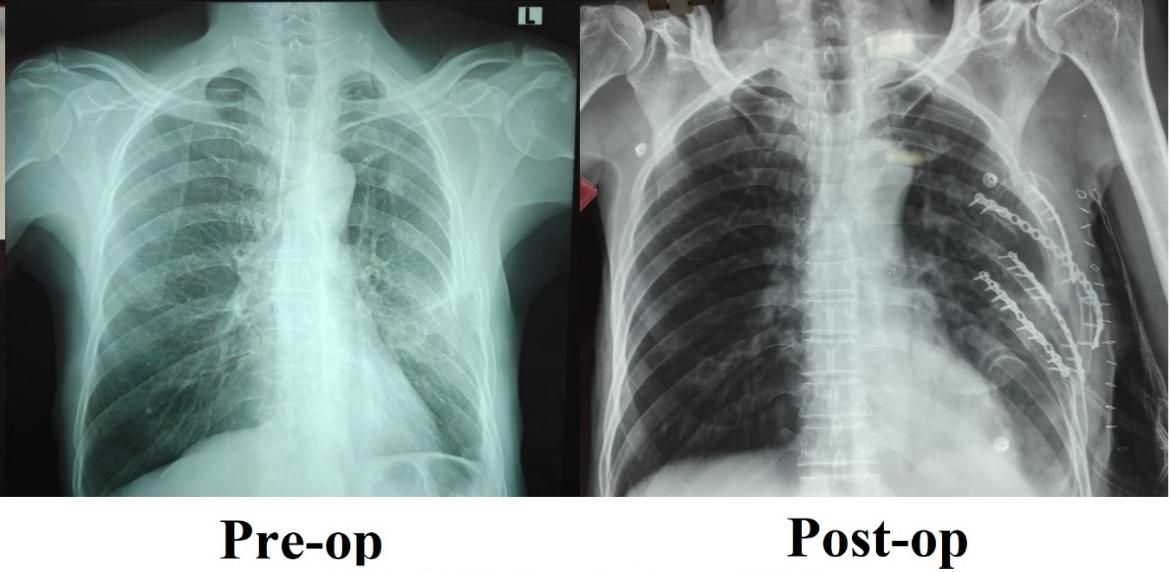

The patient, who had sustained multiple rib fractures in a road traffic accident, continued to suffer from severe chest pain for over a month despite optimal pain management and structured physiotherapy. The condition led to difficulty in deep breathing, disturbed sleep, and restricted daily activity due to poor healing and instability of the fractured ribs.

Recognising the need for surgical intervention, the trauma team led by Dr. Vijayan P, Associate Professor, Department of General Surgery, undertook a specialised rib fixation procedure to realign and stabilise the fractured ribs, enabling proper anatomical healing.

Following surgery, the patient showed rapid and marked improvement. Breathing became comfortable, mobility improved significantly with minimal pain, and the patient was able to resume routine activities with renewed confidence.